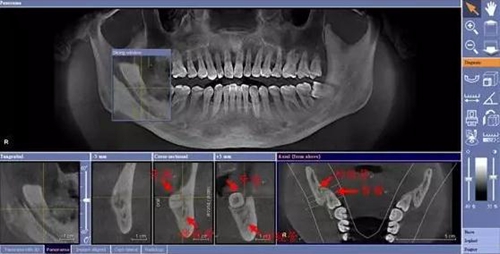

下面這兩張圖,據(jù)說拔牙費(fèi)時(shí)1.5小時(shí),收費(fèi)14000元。

在比如智齒:

由于智齒的生長位置特殊,導(dǎo)致了拔除難易不同,如智齒出現(xiàn)橫著長或者靠近牙神經(jīng)的話,則難度會(huì)較高,一般人只需拍個(gè)口腔全景片,但相對(duì)于智齒靠近神經(jīng)管的情況,還可能需要拍CT,這都很考驗(yàn)牙醫(yī)的技術(shù)。